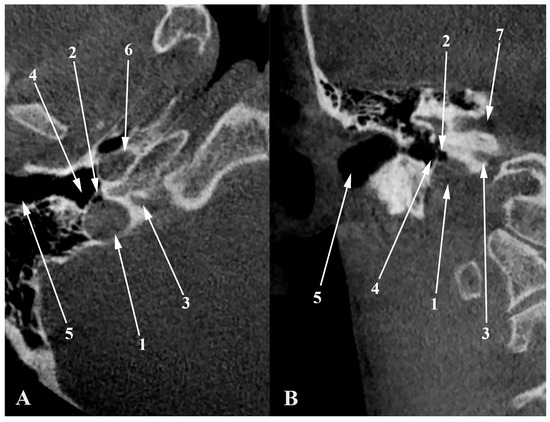

4. High Jugular Bulb

5. Dehiscent Jugular Bulb